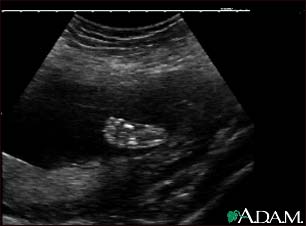

Ultrasound, normal fetus - foot

This is a normal ultrasound of a fetus at 19 weeks gestation. The right foot, including the developing bones, are clearly visible in the middle of the screen.